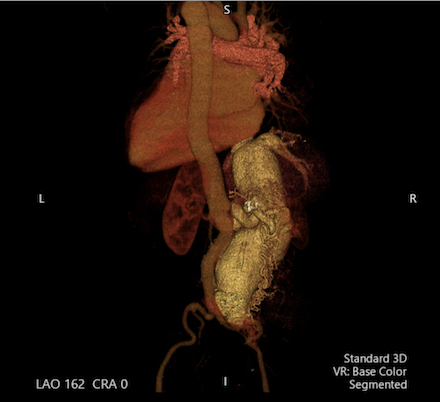

Abdominal computed tomography venogram showed dilation of the IVC up to 8cm and an aortocaval fistula at the level of the right renal vessels, resulting in an atrophic right kidney. Cardiac catheterization was notable for a cardiac output (CO) of 12L/min, cardiac index (CI) of 7L/min/m2 and reduced systemic vascular resistance (SVR). He was managed with beta blockers and diuretics, followed by TEE-guided cardioversion for atrial flutter to restore sinus rhythm. Vascular surgery performed a successful, first of its kind endovascular repair of the abdominal aorta with stenting of the right common iliac artery and placement of a 20mm Amplatzer Septal Occluder device in the right renal artery. He tolerated the procedure well, and post-operative TTE showed a recovered LVEF of 55-60% and CO of 6L/min.